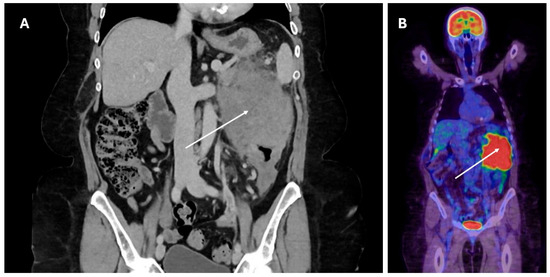

The significant majority (n = 24, 85.7%) of patients presented with visceral disease, with the remaining four (14.3%) patients presenting with nodal-only disease. Of those with visceral disease, the most involved organ was the bowel (n = 9, 37.5%), followed by the central nervous system (CNS) (n = 6, 25%) and soft tissue (n = 4, 16.7%). There were single (4.2%) cases involving the bone, bone marrow, lung, and spleen. Only one case involved the liver allograft itself. The mode of presentation reflected the involved organs, such that patients with bowel disease presented with a range of symptoms including abdominal pain, gastrointestinal bleeding, bowel obstruction, and loss of weight. Those with primary CNS disease presented with focal neurological symptoms or seizures. A typical diagnostic computed tomography (CT) scan and positron emission tomography (PET) scan for a patient presenting with PTLD involving bowel are presented in Figure 1, with the histology presented in Figure 2.

Figure 1. PTLD presenting with mass (arrow) involving descending colon and small intestine visible on CT (panel (A)) with corresponding PET scan image (panel (B)).